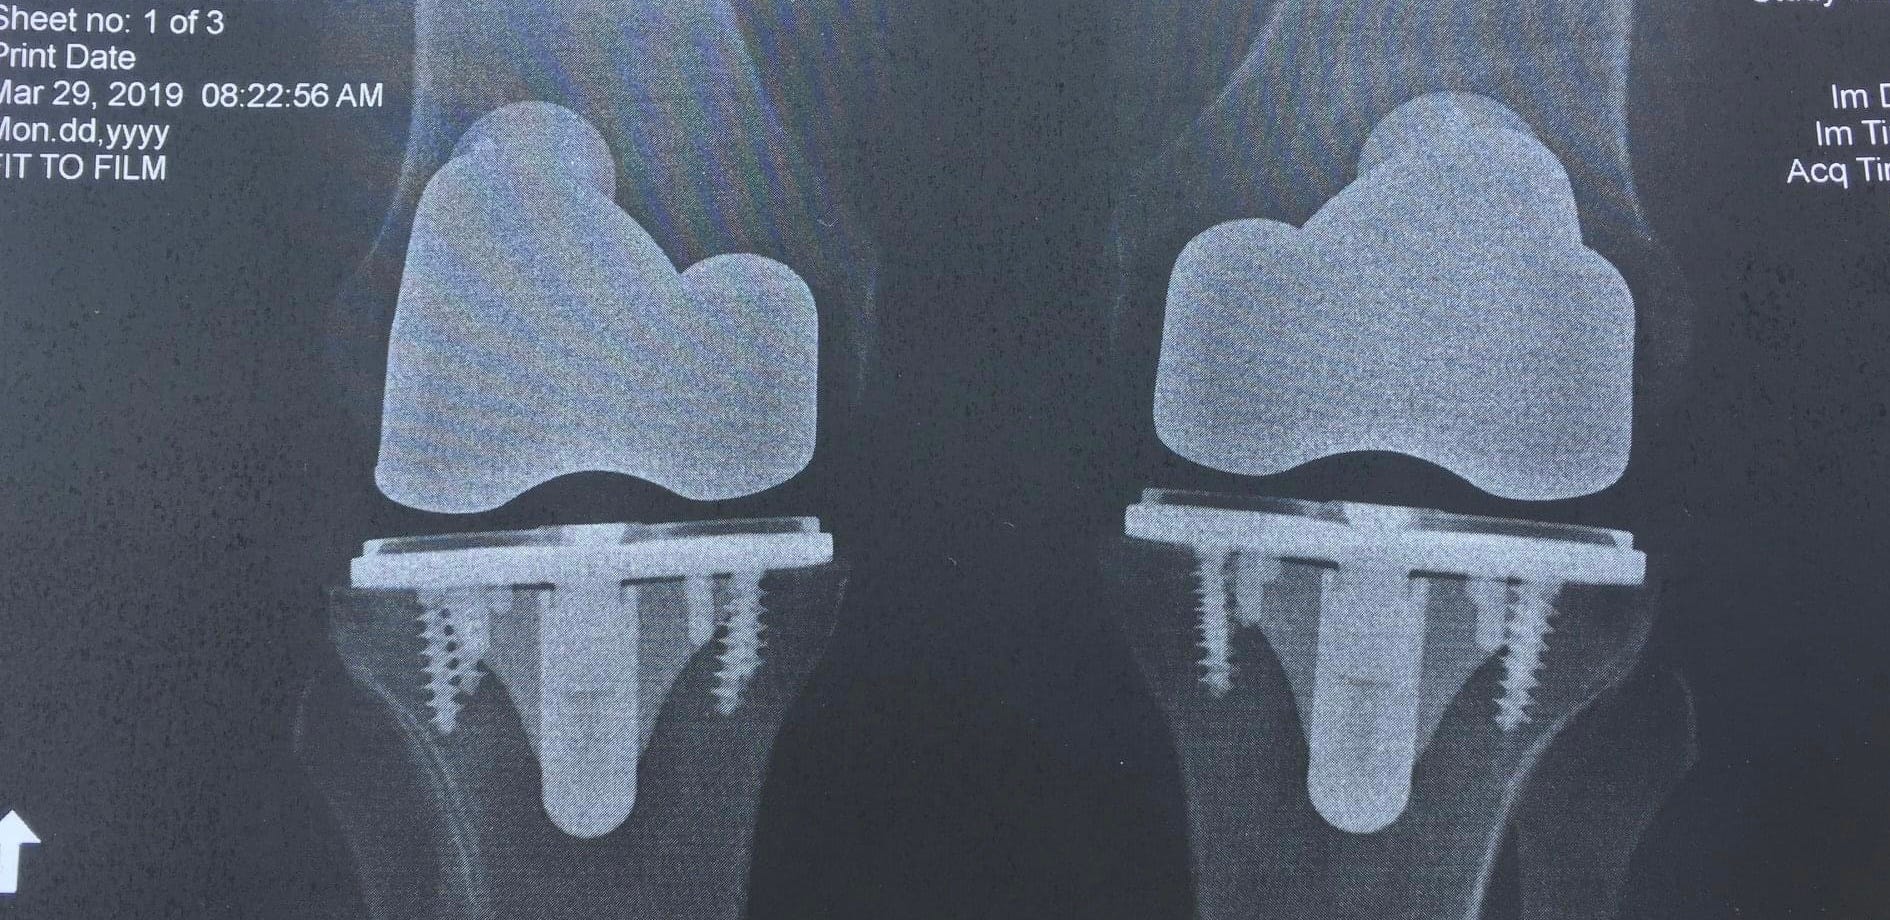

Days of excessive mud, elevation change, blisters, hunger, or overall fatigue bring to mind just how complicated those seemingly autonomous gestures are to affect. Time also plays a fundamental role— the slow degradation of bodily function across a long hiking day, a long hiking season, or a lifetime of wear and tear. On the Appalachian Trail, hikers are given trail names. You cannot name yourself but instead are nominated by a trail colleague. Mine was “Tin Man” because a month before I started hiking I’d had surgery to clean up (that felicitous term debride) one of my knees. The surgeon recommended I return every two weeks for a shot, and since the first weeks of the AT are still fairly close to my hometown, Atlanta, I was, with the help of friends and family, able to get back from the trail for a lube job— hence my sobriquet. As the years and many other long distance trails passed, my bow legs stressed my knees and the arthritis increased. This time a tuneup and lube job were not possible, so I went in for total knee replacement— first one, then 4 months later the other. A year of rehab which for me meant miles of city walking, and I was ready to test the modifications.